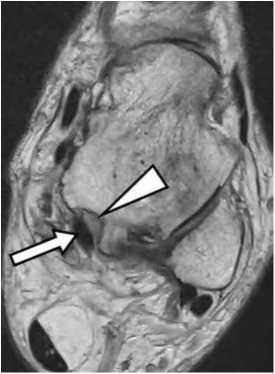

На МРТ обычно визуализируются жидкостной компонент и синовиальные разрастания в проекции дистальной части межберцового синдесмоза, внутри канала латеральной лодыжки, по передней и задней поверхностям голеностопного сустава, по ходу таранного синуса, которые имеют среднюю и высокую интенсивность сигнала в PD FSE импульсных последовательностях и отчетливо выявляются на томограммах с подавлением сигнала от жира (рис. 5).

Рис. 5. Сочетание заднего импинджмент-синдома и синдрома таранного синуса у профессионального спортсмена с жалобами на боль в голеностопном суставе без анамнеза острой травмы.

А: Сагиттальная FS PD FSE томограмма показывает синовиальные кистозные разрастания по задней поверхности голеностопного сустава (треугольная стрелка) и в проекции таранною синуса (обычная стрелка).

Б: синовиальные кисты в нижней части межберцового синдесмоза (треугольные стрелки) на PD FSE томограмме в аксиальной проекции.

В: синовиальные кисты в проекции таранного синуса (обычная стрелка) на PD FSE томограмме в аксиальной проекции. Тот же пациент.